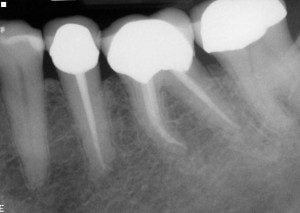

end-case-2-a